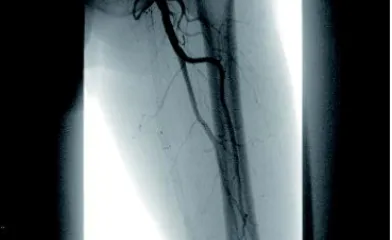

ケースレポート実際の臨床応用を通じて、製品への理解をさらに深めてください。 製品に関連するケースレポートをご覧ください並び替え昇順降順並び替え 昇順降順ポートフォリオ大動脈領域末梢血管領域ポートフォリオ 大動脈領域末梢血管領域関連製品ゴア® TAG® コンフォーマブル 胸部大動脈ステントグラフト アクティブコントロールシステムゴア® エクスクルーダー® IBEゴア® エクスクルーダー® コンフォーマブル AAAステントグラフト アクティブコントロールシステムゴア® バイアバーン® VBX バルーン拡張型ステントグラフト ゴア® バイアバーン® ステントグラフト関連製品 ゴア® TAG® コンフォーマブル 胸部大動脈ステントグラフト アクティブコントロールシステムゴア® エクスクルーダー® IBEゴア® エクスクルーダー® コンフォーマブル AAAステントグラフト アクティブコントロールシステムゴア® バイアバーン® VBX バルーン拡張型ステントグラフト ゴア® バイアバーン® ステントグラフト治療領域末期腎不全末梢血管疾患胸部大動脈疾患腹部大動脈瘤血管損傷治療領域 末期腎不全末梢血管疾患胸部大動脈疾患腹部大動脈瘤血管損傷 34 結果 Image 6 Fr 対応ゴア® バイアバーン® VBXバルーン拡張型ステントグラフトを用いた橈骨動脈アプローチによる腸骨動脈 EVTの一例 さらに詳しくImage AVGの人工血管延長術後に生じた再流出路狭窄症例に対してゴア® バイアバーン® ステントグラフトを挿入した一例 さらに詳しくImage DESによる左浅大腿動脈の慢性閉塞の治療後、コロナ禍の受診中断でステント内閉塞となり再来された一例 さらに詳しくImage SFAの長区域閉塞病変にゴア® バイアバーン® ステントグラフトを留置し、3年フォローした一例 さらに詳しくImage SFA入口部からの長区間超高度石灰化閉塞病変に対して外科的内膜摘除術との併用でゴア®バイアバーン® ステントグラフトを留置し、6か月フォローした一例 さらに詳しくImage SFA起始部のランディングに悩むCTO病変に対しゴア® バイアバーン® ステントグラフトを用いてEVTを完遂し、2年経過を観察した一例 さらに詳しくImage Shaggy Aortaを合併した遠位弓部大動脈瘤に対するTEVAR さらに詳しくImage ケースレポート:ゴア® TAG® コンフォーマブル 胸部大動脈ステントグラフト アクティブコントロールシステム さらに詳しくImage ケースレポート:ゴア® エクスクルーダー® IBE さらに詳しくImage ケースレポート:ゴア® バイアバーン® VBX バルーン拡張型ステントグラフト さらに詳しくImage ケースレポート:ゴア® バイアバーン® ステントグラフト さらに詳しくImage ケースレポート:外傷性胸部大動脈損傷に対するゴア® TAG® コンフォーマブル 胸部大動脈ステントグラフト アクティブコントロールシステムの有用性 さらに詳しくImage ゴア® TAG® コンフォーマブル 胸部大動脈ステントグラフト アクティブコントロールシステムの特徴および有用性 さらに詳しくImage ゴア® バイアバーン® ステントグラフトの使い所 –長期開存したISO症例– さらに詳しくImage ゴア® バイアバーン® ステントグラフトを人工血管内シャント静脈側吻合部狭窄のリコイルに対して用いた症例 さらに詳しく さらに表示 トップ